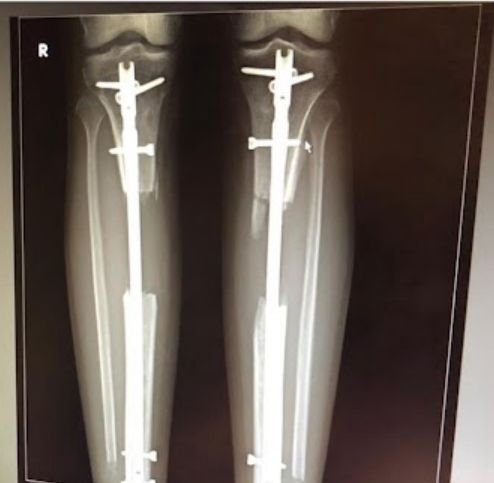

Limb Lengthening